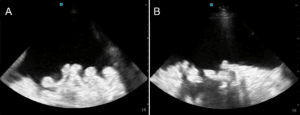

A 59-year-old man, with known alcohol-induced liver cirrhosis and diuretic refractory ascites, was seen in General Internal Medicine clinic for a therapeutic paracen­tesis. The tense large volume ascites caused abdominal pain, which had been previously relieved with paracen­tesis on several occasions. In preparation for paracen­tesis, routine POCUS was performed to landmark for the procedure. POCUS revealed an unexpected thin-walled mobile structure (Figure 1) within the abdominal cavity (online Video S1). There was no history of abdominal surgery, or any indwelling catheters.

Figure 1. Point of Care Ultrasound of Right Lower Abdominal Quadrant. Four still images captured from the 6 seconds of video recording.